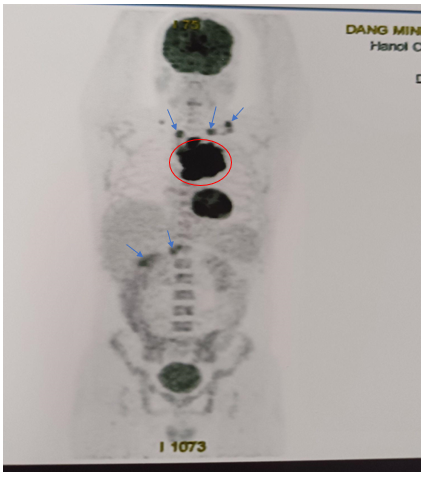

-         Hình ảnh chụp PET/CT đánh giá giai đoạn trước điều trị (tháng 5/2024)

·        Hạch nền cổ, thượng đòn 2 bên, lớn nhất ~ 28x18mm (SUVmax: 10.47).

·        Khối lớn ở trung thất trước, lệch trái kích thước ~84x109x90mm, phá hủy xương ức,cung trước xương sườn 3 trái, thành ngực trước trái, xâm lấn quai động mạch chủ (SUVmax: 17.88).

·        Vài hạch trung thất, lớn nhất 14x17mm (SUVmax: 3.17). Hạch rốn gan, hạch bẹn. Tăng nhẹ chuyển hóa FDG lan tỏa ở hệ thống xương.

Hình 2: Hình ảnh tăng chuyển hoá FDG ở nhiều vị trí khối lớn ở trung thất trước, hạch cả ở trên và dưới cơ hoành, tăng FDG lan tỏa hệ thống xương.